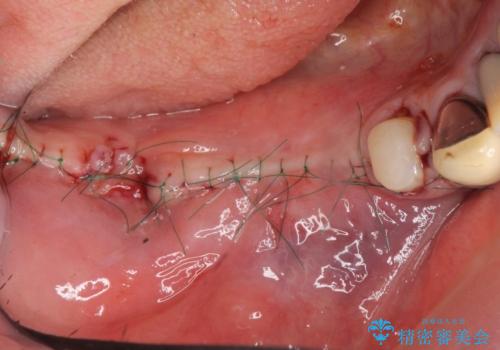

また骨の問題だけでなく、完成後に歯ブラシがしやすいよう歯ぐきの移植も行いよりインプラント周囲の環境が安定するよう環境を整える治療計画を立てます。

また、機能したインプラントを長持ちさせるために清掃性を高めるために硬い歯ぐきを移植することは非常に有効です。